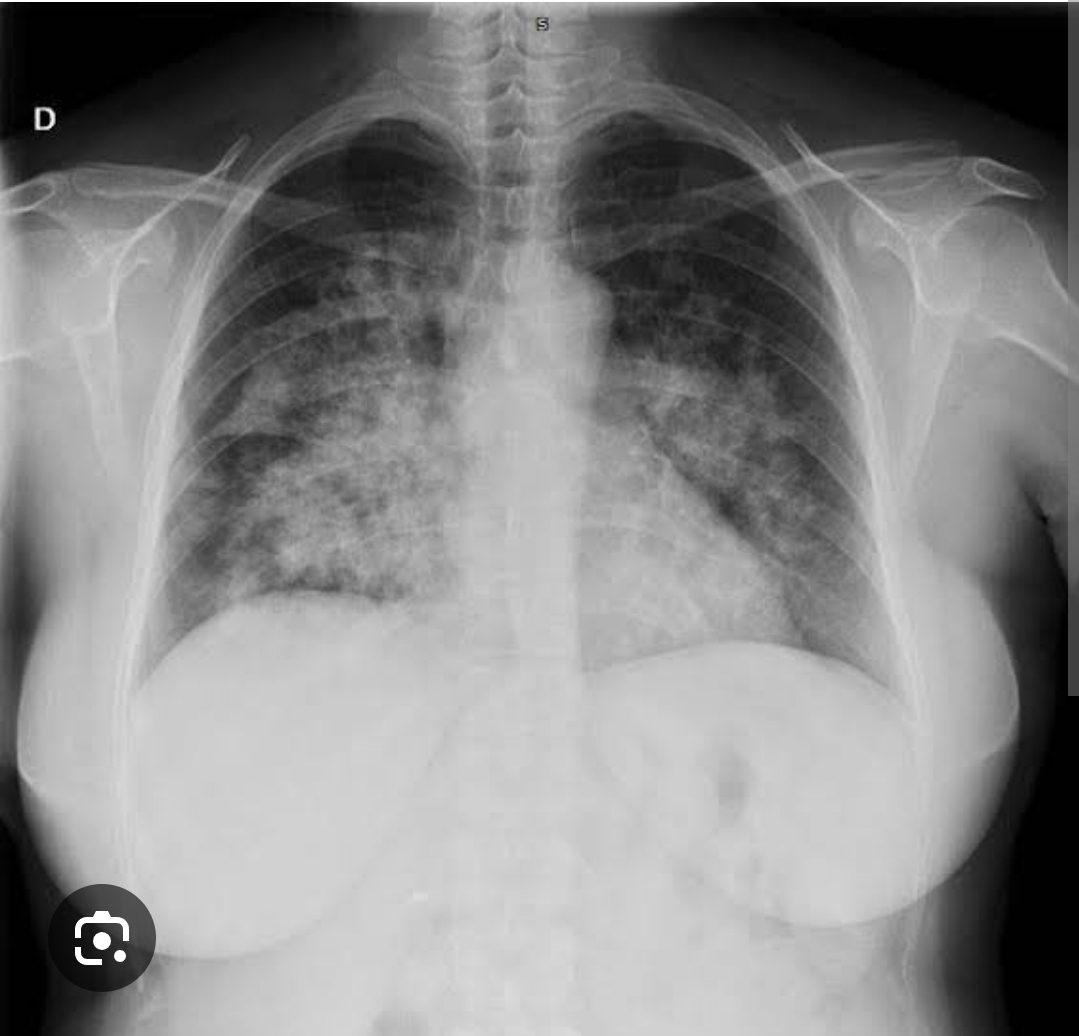

Quais são as alterações difusas de atenuação/opacidade?

A

1) infiltrado alveolar

2) infiltrado intersticial/reticular

3) infiltrado miliar/micronodular